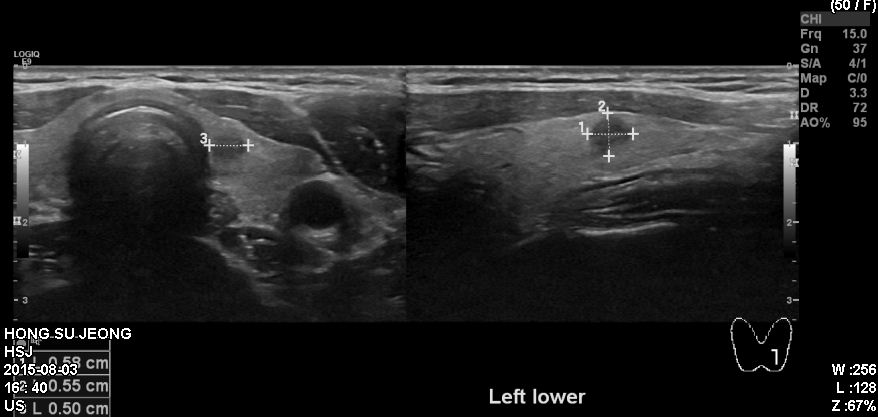

MRI 검사상 갑상선의 이상소견이 있어 정밀검사 위해 내원하신 50대 여성으로 본원 초음파  시행후 좌측 갑상선의 의심되는 혹 세포검사 시행하여 갑상선 유두암 진단 되었습니다.